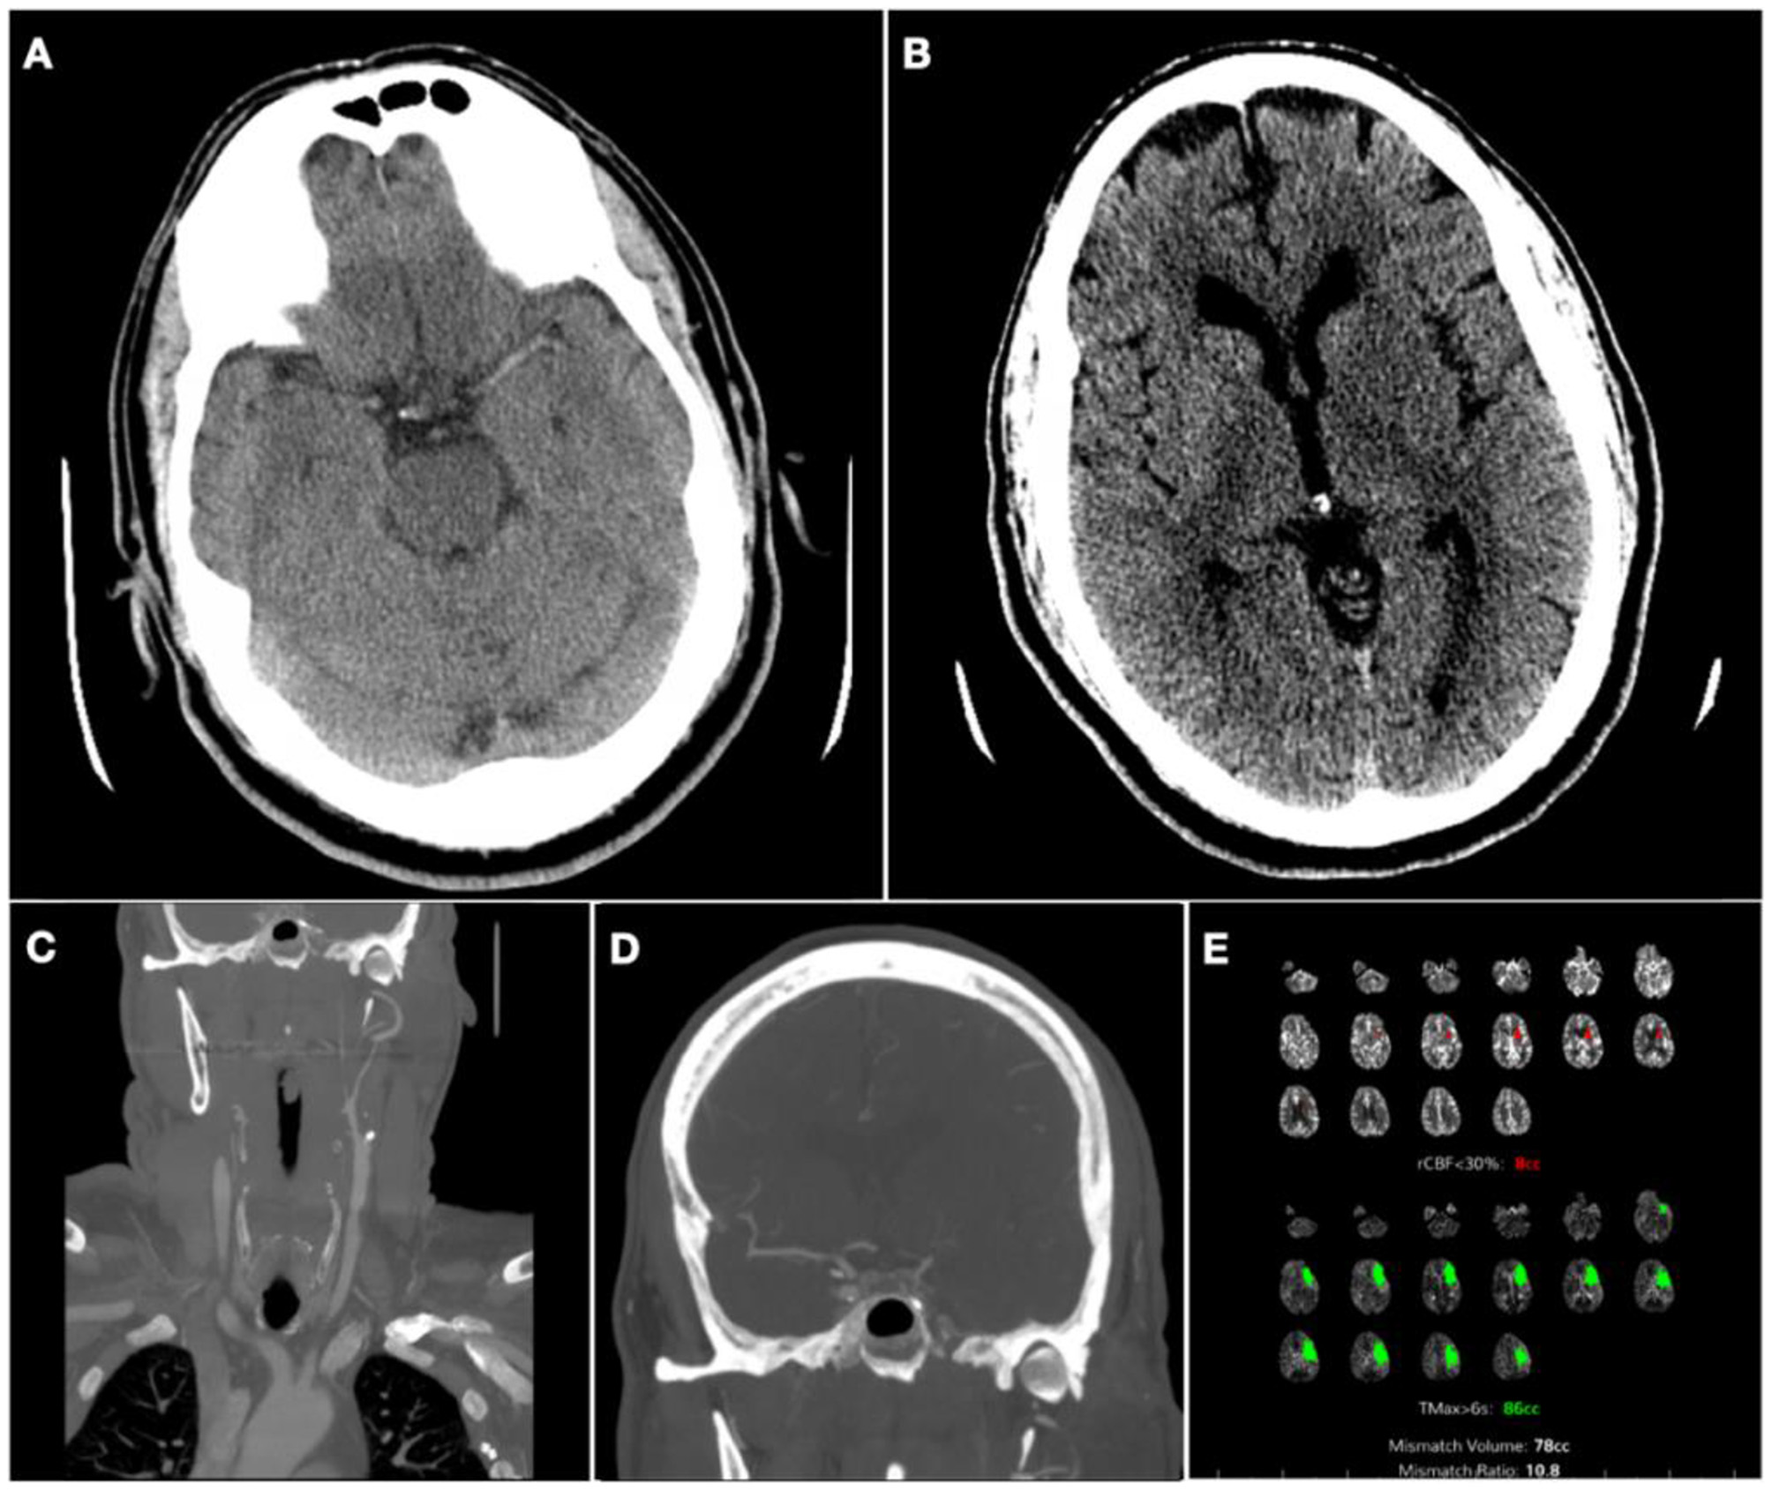

During the cerebral angiogram, performed under moderate sedation, he was noted to have progressive improvement of symptoms, with near-total resolution of expressive aphasia and dysarthria and an NIHSS score of 3. Digital subtraction images revealed a near-complete occlusion of the proximal left ICA (Figure 2A), with tandem occlusion of the left terminal ICA (Figure 2B). There was flow to the MCA territory through leptomeningeal collaterals from the posterior cerebral arteries (Figure 2C). There was also severe proximal right ICA stenosis (Figure 2D). There was partial collateral flow to the left terminal carotid branches via the patent anterior communicating complex (Figure 2E) and leptomeningeal collaterals off the left anterior cerebral arteries (Figure 2F). The risks of acute endovascular intervention were deemed to outweigh the benefits in the setting of rapidly improving symptoms and NIHSS score of 3, upon partial recanalization after IVT, so the procedure was aborted.

Figure 2. Digital subtraction angiogram at initial presentation. (A) Left common carotid artery (CCA) injection, neck lateral view; (B) Left CCA injection, head anterior-posterior (AP) view showing non-opacification of terminal left internal carotid artery (ICA); (C) Left vertebral artery injection, head AP view, with collateral supply to middle cerebral artery (MCA) territory on late arterial phase (ellipse); (D) Right CCA injection, neck lateral view; (E) Right CCA injection, head AP view showing cross-filling of L anterior cerebral artery on early arterial phase; (F) Right CCA injection, head AP view showing collateral supply to MCA territory on late arterial phase (rectangle).